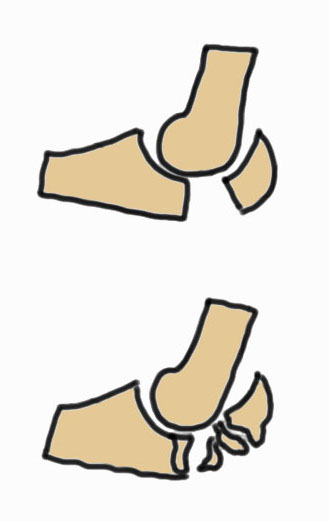

Mayo Classification

A: Non comminuted

B: Comminuted

| Type I | Type II | Type III |

| Minimally displaced | Displaced | Trans-olecranon fracture dislocation |

| 10% | 85% | 5% |